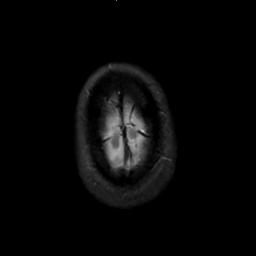

MR Study #1, February 10, 1991 -- Slice #47

[Home][Help][Clinical][Tour 1][Tour 2] Slice 47